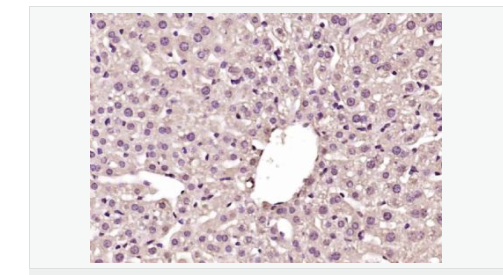

| 產(chǎn)品應(yīng)用 | WB=1:500-2000 ELISA=1:5000-10000 IHC-P=1:100-500 IHC-F=1:100-500 IF=1:100-500 (石蠟切片需做抗原修復(fù)) not yet tested in other applications. optimal dilutions/concentrations should be determined by the end user. |